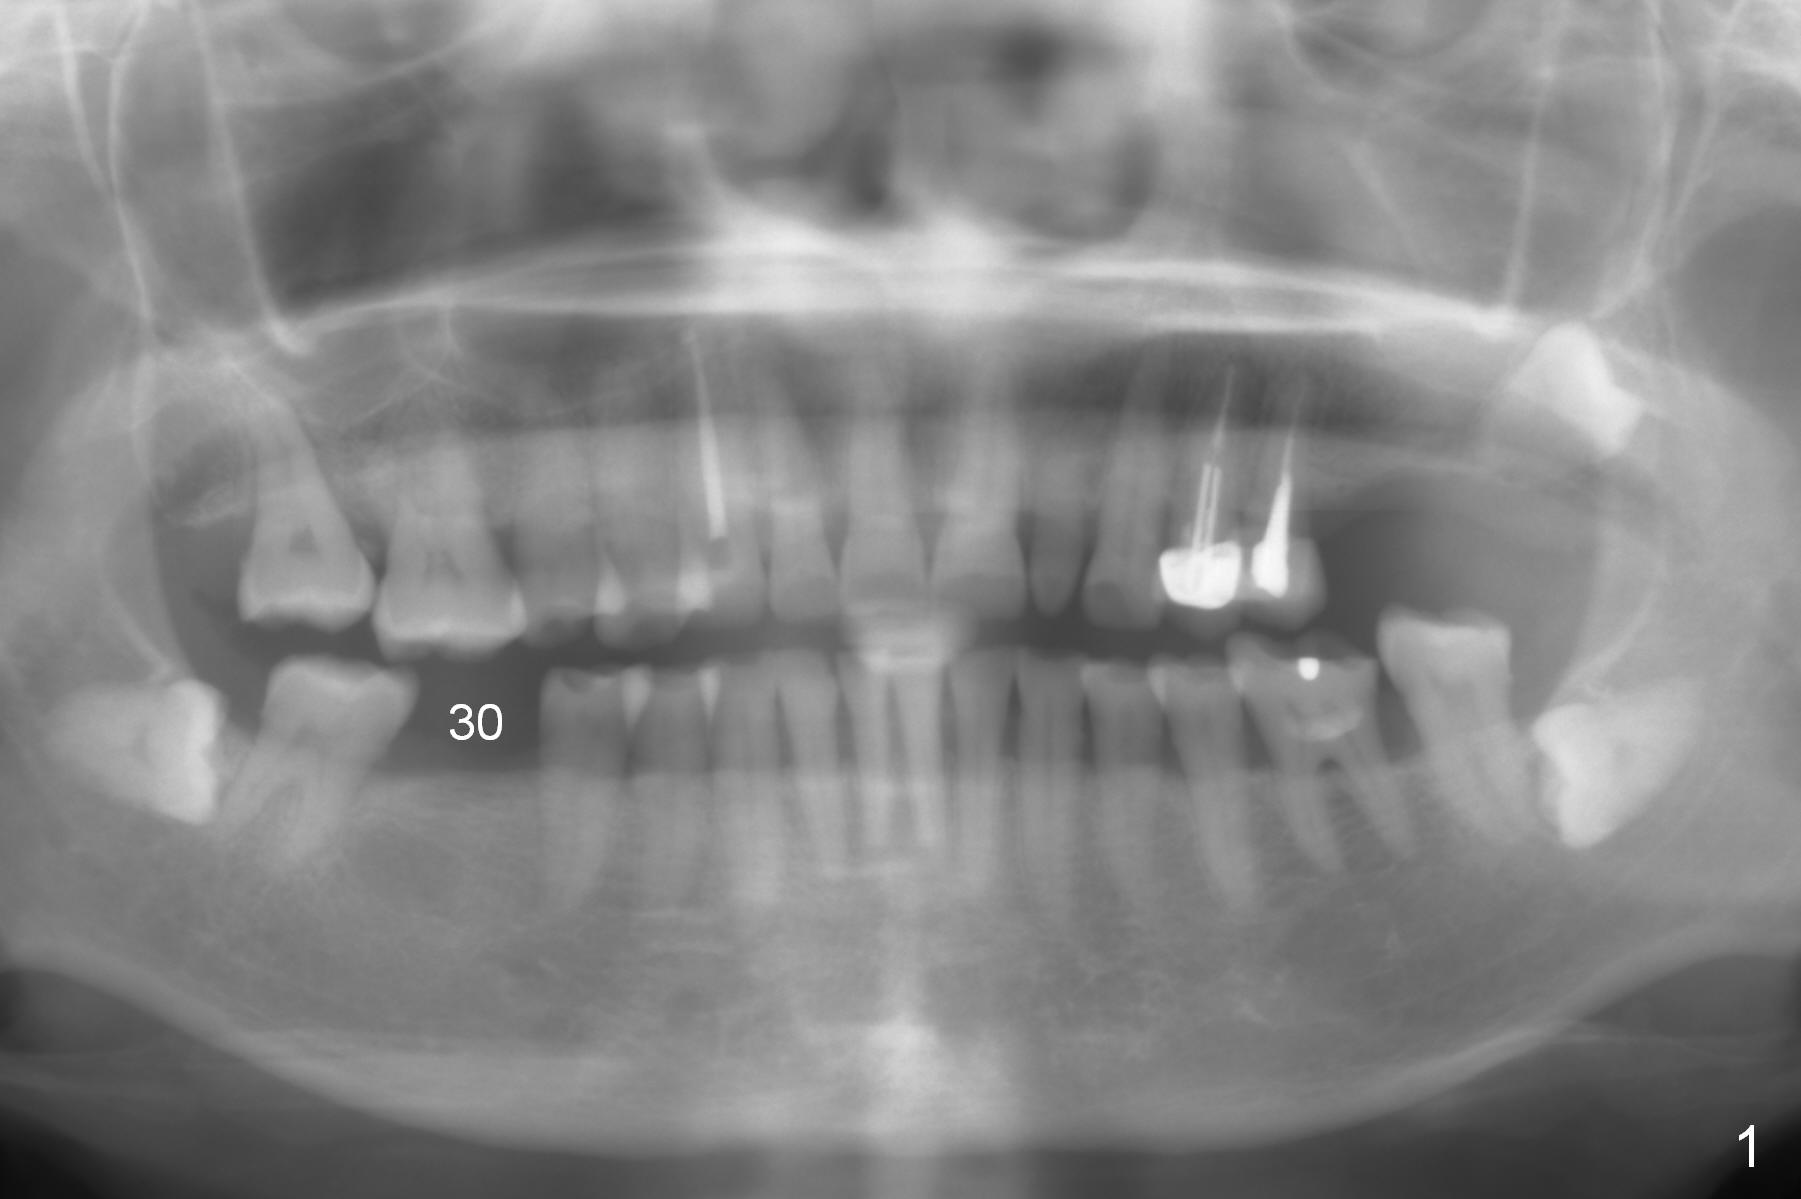

A 57-year-old woman has 3 missing molars, including #30 (Fig.1). Although she looks skinny, clinically the ridge is moderately wide. Magic Split will be used for access (flapless) and bone density testing. From PA, the bone density does not seem to be low (Fig.2). Use the 1.6 mm drill without stopper for further bone density testing. The initial depth will be 15 mm (gingival level, Fig.3). After PA confirmation of the trajectory, use 3.8 mm Magic Drill for 15 mm. Try 4.5x11 mm dummy implant, followed by PA. When an abutment is placed, trim the opposing surpraerupted tooth if necessary (Fig.3 arrow).